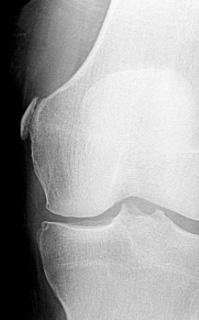

Чаще всего изменения при МРТ колена рассматриваются как симптомы артроза, особенно если в анамнезе отсутствовали травмы. Кальцификация может локализоваться вдоль медиального мыщелка в мягких тканях, что делает её визуализацию на МРТ коленного сустава невозможной. В то же время на стандартных рентгенографиях в прямой проекции данная патология хорошо отчетливо видна.

Рентгеновский снимок коленного сустава в прямой проекции. Болезнь Пеллигрини-Штиды.